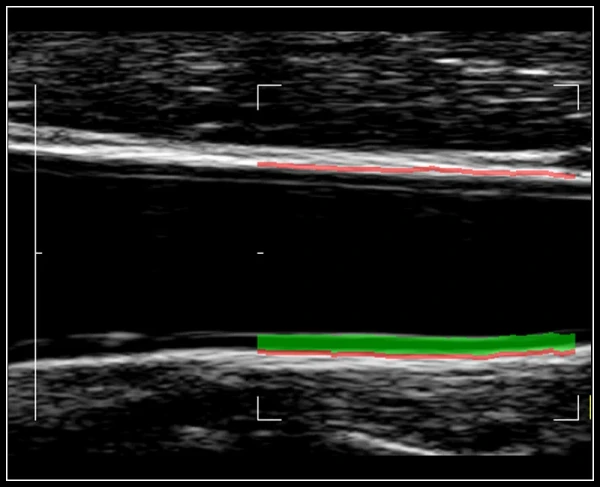

Monokristalli texnologiya skanerlash chuqurligidan qat'iy nazar aniq signalni qabul qilishni ta'minlaydi

Yuqori zichlikdagi faol matritsali kompozit materiallar mukammal piksellar sonini va ajoyib tasvir kontrastini kafolatlaydi

Ko'p moslashuvchan qatlamlar artefakt va shovqin miqdorini kamaytiradi